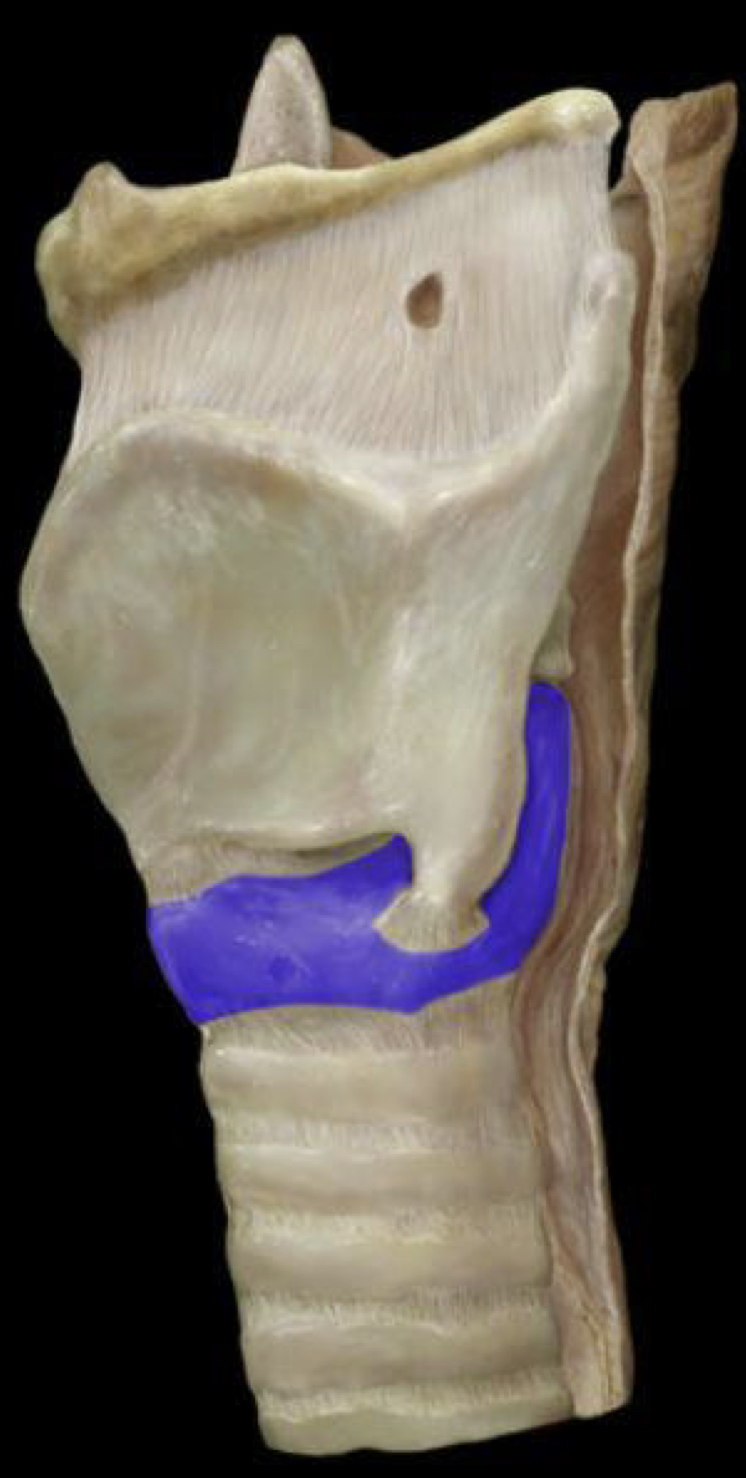

What structure is highlighted in blue?

Cricoid cartilage (lateral view)